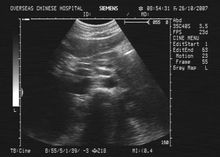

B超BUS檢查

B超BUS檢查具有無創、安全、快速、廉價及重複性好的特點,常作為首檢查方法,並具有篩選價值,B超是診斷的首選方法。主要圖像特徵有以下幾點: (1)多數患者有膽囊結石,結石位於膽囊或膽囊頸部,膽囊壁增厚,膽囊可見擴張、萎縮或膽囊大小正常。

(2)膽囊管開口上方的肝總管、肝內膽管擴張或不擴張。

(3)膽總管直徑大小正常。

Joseph描述膽總管直徑正常,可見到擴張的膽囊管、肝總管及門靜脈,即所謂的“三管征”(triplechannelsign)。 見到“三管征”應考慮為硬化性膽管炎,但是臨床上很少見到“三管征”。何效東等報導32例中23例行B超檢查,僅有2例出現“三管征”。肝總管狹窄及膽囊膽管瘺患者,由於患者的膽囊萎縮,顯像不佳,再加之膽總管顯示不清,較難判斷。Ⅰ型嵌頓結石均容易顯示。文獻認為凡是臨床有反覆發作的膽管炎、梗阻性黃疸而超聲顯示膽囊頸或膽囊管結石,膽囊壁增厚的患者,特別是BUS診斷同時發現肝總管及肝內膽管擴張而膽總管不擴張者應高度懷疑本病的可能。